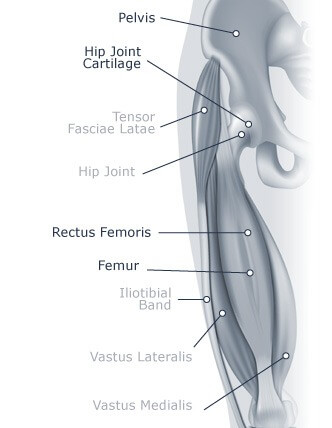

Inflammatory arthritis may be accompanied by dull joint pain in the groin, outer hip and buttocks. Activity may increase pain. Osteoarthritis in the hip occurs when the cartilage on either the femoral head, or within the socket begins to thin. Osteoarthritis can be caused by heredity, age, obesity or injuries that cause tension in the cartilage. Osteoarthritis may cause stiffness and pain in the hip area. Prolonged osteoarthritis may lead to pain while moving as the cartilage continues to grow thinner.

Osteonecrosis is caused by a lack of blood supply to the hip joint. Without blood, the femoral head begins to deteriorate which can then cause the cartilage surrounding it to break down, leading to arthritis. This condition can be caused by hip dislocations, fractures, other injuries that harm the femoral head, alcoholism, corticosteroid medications, and other medical conditions. This condition may result in pain in the hip and buttock region and increased pain when standing and moving. Osteonecrosis usually progresses over a time span of a few months to a year.

Many muscles, including the rectus femoris, surround the hip bones and the hip joint. When these muscles are strained, discomfort results. Hip strains can be caused by a lack of stretching and warming up before physical activity. They can also be caused from overusing or overstretching the muscles. Hip strains may lead to pain, swelling and weakness in the area of the strained muscle.